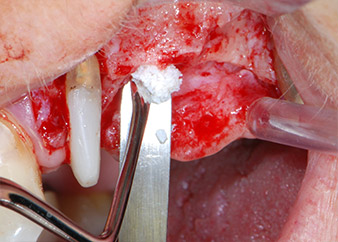

Prior to implant placement, and following verification of an intact Schneiderian membrane (Fig. 9), the internal sinus floor was augmented at both implant sites by means of xenogeneic bone substitute material (Bio-Oss, Geistlich Biomaterials) (Fig. 10).